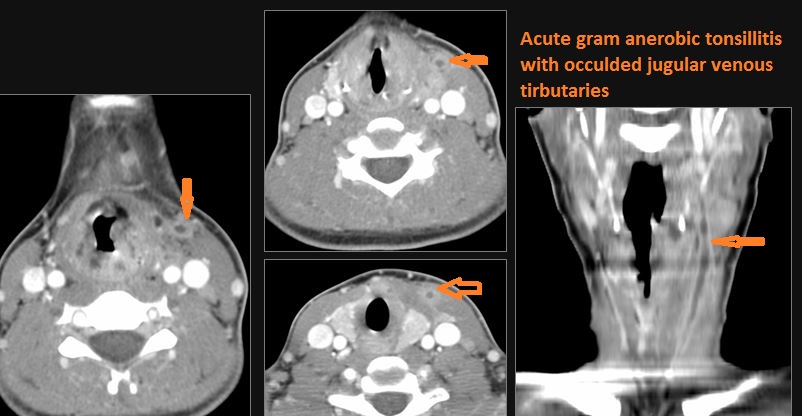

There is evidence of thrombus, thrombophlebitis or other occlusive or inflammatory process of the jugular vein. [Yes/No]

There is evidence of thrombus, thrombophlebitis or other occlusive or inflammatory process of smaller jugular venous tributaries. [Yes/No]